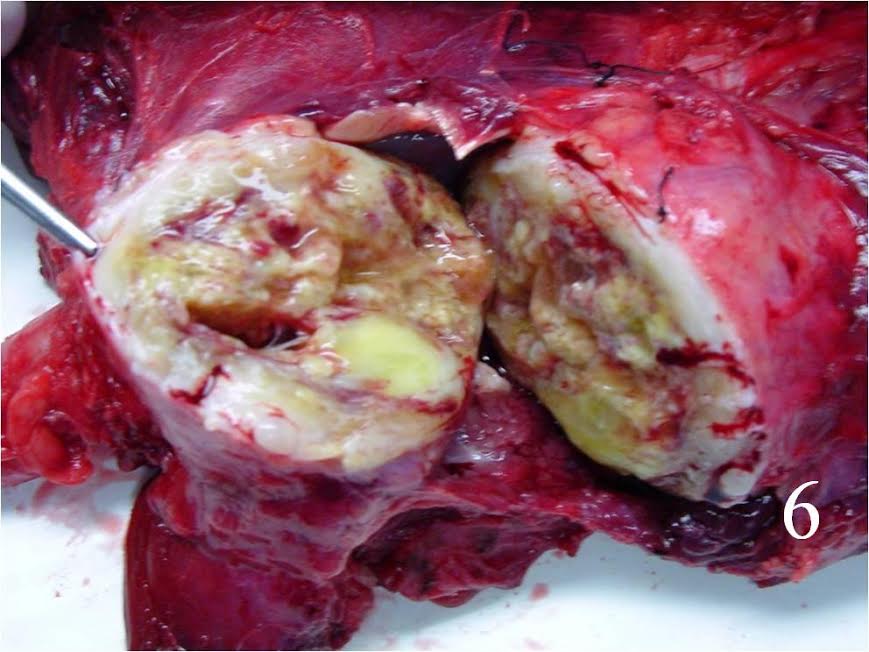

Gross

- Fleshy, white-tan surface marked by areas of secondary hemorrhage and necrosis (Fig. 6)

- Usually large than 5cm in diameter

- Spread of the tumor demonstrated for the thickening of the nerve proximally and distally to the mass. Tumor spread appears as thickening of nerve proximal and distal to the mass